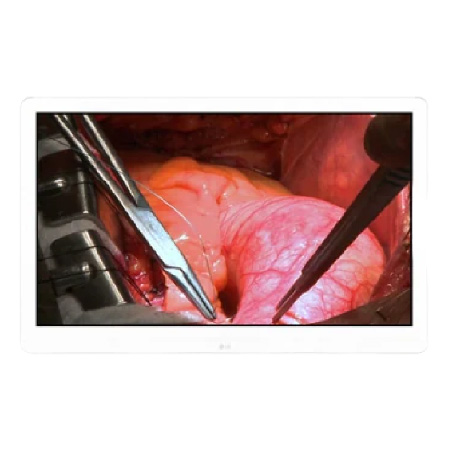

Cirugía

La pantalla ideal para una cirugía detallada; consigue los mejores resultados con una calidad de imagen, facilidad de uso y credibilidad excepcionales. Ideal para Endoscopia, Colondoscopia, Lamparoscopia, cirugia).

Monitor quirúrgico LG 31.5″ 4K IPS.

- 31.5″ (80.01 cm) 4K (3840×2160) IPS